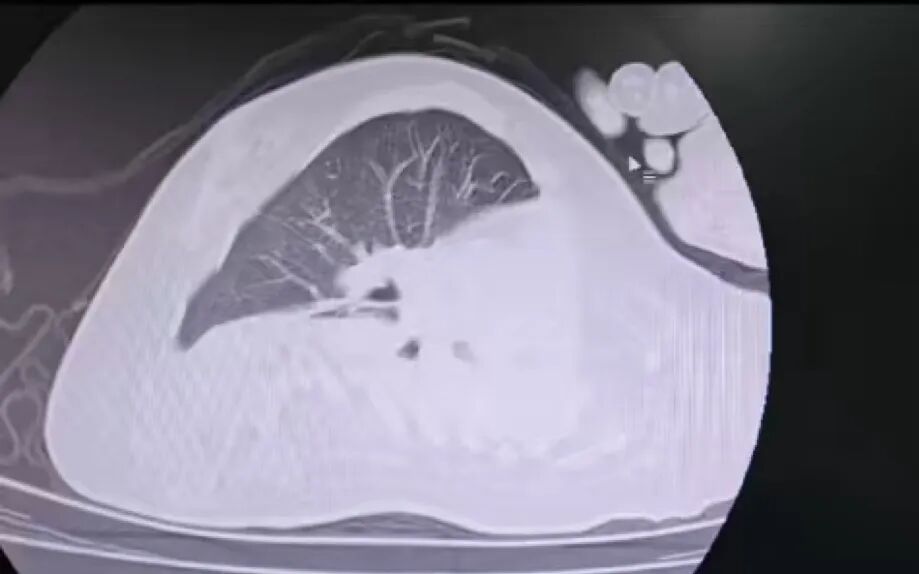

治療前

該患兒因患脊髓性肌萎縮癥長(zhǎng)期臥床,呼吸肌已嚴(yán)重?zé)o力,自主呼吸微弱且?guī)缀鯁适Э人耘盘的芰?,此次并發(fā)支氣管肺炎后,肺部感染迅速加重,生命已然懸于一線。更棘手的是,嚴(yán)重的脊柱側(cè)彎使患兒胸廓畸形、氣道解剖結(jié)構(gòu)明顯移位,常規(guī)纖支鏡進(jìn)鏡路徑完全失效,扭曲狹窄的氣道如同縱橫交錯(cuò)的“迷宮”,每一步操作都必須精準(zhǔn)到毫米級(jí)別。

體位擺放則成為另一道“攔路虎”,既要滿足纖支鏡操作需求,又要避免側(cè)彎脊柱受壓、防止肌萎縮引發(fā)關(guān)節(jié)脫位,每個(gè)角度都得反復(fù)測(cè)算。同時(shí),還需直面層層疊加的術(shù)中危機(jī):因患兒呼吸肌功能幾乎喪失,纖支鏡占用狹窄氣道空間后,缺氧、二氧化碳潴留及急性呼吸衰竭、心跳驟停風(fēng)險(xiǎn)陡增;灌洗過程中若液體殘留將加重肺部感染,而患兒免疫力低下,導(dǎo)致敗血癥的風(fēng)險(xiǎn)顯著升高。